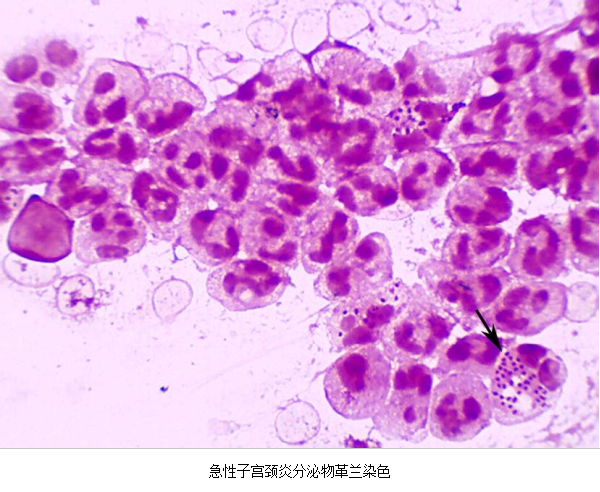

(1)子宫颈管脓性分泌物涂片作革兰染色,中性粒细胞>30/高倍视野。

急性子宫颈炎患者,子宫颈管脓性分泌物涂片作革兰氏染色,中性粒细胞>30/高倍视野,

箭头处为中性粒细胞内可见革兰氏阴性双球菌

3.病原体检测 应作衣原体及淋病奈瑟菌的检测,以及有无细菌性阴道病及滴虫阴道炎。检测淋病奈瑟菌常用的方法有:①分泌物涂片革兰染色,查找中性粒细胞内有无革兰阴性双球菌,由于子宫颈分泌物的敏感性、特异性差,不推荐用于女性淋病的诊断方法。②淋病奈瑟菌培养,为诊断淋病的金标准方法。③核酸检测,包括核酸杂交及核酸扩增,尤其核酸扩增方法诊断淋病奈瑟菌感染的敏感性及特异性高。检测沙眼衣原体常用的方法有:①衣原体培养,因其方法复杂,临床少用。②酶联免疫吸附试验检测沙眼衣原体抗原,为临床常用的方法。③核酸检测,包括核酸杂交及核酸扩增,尤以后者为检测衣原体感染敏感、特异的方法。但应做好质量控制,避免污染。